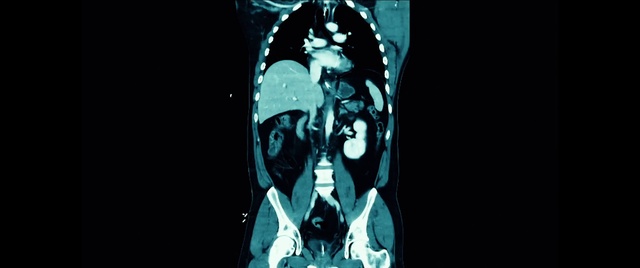

Best Video References: Stomach ache